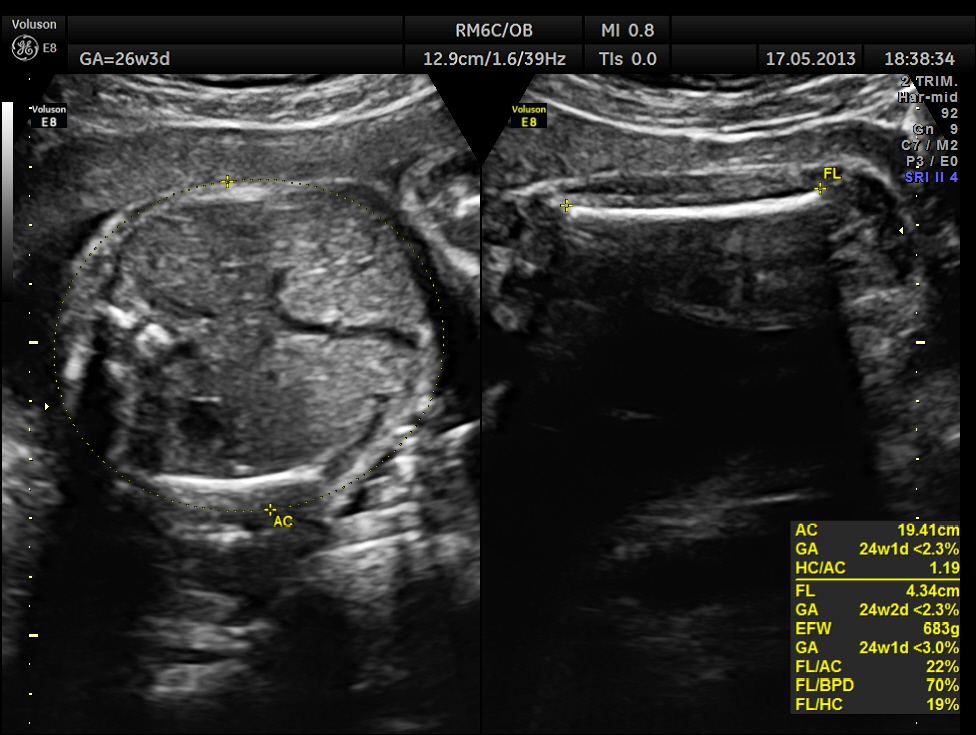

The abdominal images are given below.

This fetus did not show any oro-facial clefts ; heart and spine appeared normal.

Cerebellum was < 2.3 %tile , suggestive of possible cerebellar hypoplasia. Unfortunately this patient was lost for follow up .